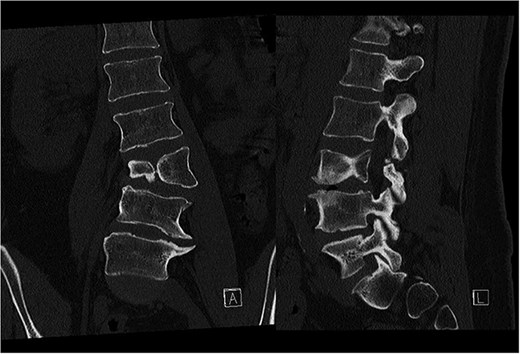

Preoperative CT demonstrating L3 hemivertebra; anteroposterior view (A) on the left side of the image, and lateral view (L) on the right side of the image.

A 24-year-old female with congenital scoliosis caused by a semi-segmented hemivertebra at L3 (Figs 4 and 5) was under follow-up at our institution for chronic back pain and left leg pain, without motor deficits. She had been referred to our institution three years earlier, at which time surgical resection was indicated. However, the procedure was postponed due to patient's personal reasons.

CT-based 3D reconstruction revealed a semi-segmented hemivertebra at L3, resulting in a 32° Cobb angle of congenital scoliosis (Fig. 4). We decided to perform hemivertebra resection, L3 laminectomy, L2-L4 fixation with L3–4 cage fusion, and scoliosis correction. CT-based resection was 3D planned using EBS software (Fig. 6). Fixation from L2 to L4 was achieved using pedicle screws under fluoroscopic guidance, followed by L3 laminectomy. After accessing the L3–L4 disc space, a 3D real-time EMN-guided total resection of the L3 hemivertebra was performed (Fig. 6), and a cage with autogenous bone graft was inserted at the L3–L4 level. The left-sided L3 nerve was found to have an accessory branch, which was successfully preserved. Scoliosis was corrected using standard deformity correction maneuvers.

Postoperatively, the patient experienced left psoas and quadriceps femoris muscle paresis, with the latter gradually improved to near-normal before discharge. No other complications were observed. At the 10-week follow-up, the left quadriceps had regained full strength, but partial paresis (3 out of 5) of the psoas muscle persisted, resulting in gait disturbance. At the final follow-up, one year after surgery, imaging showed L2-L4 fusion with no signs of instability or residual deformity (Fig. 4). The patient’s back pain resolved. A normal muscle function was observed.